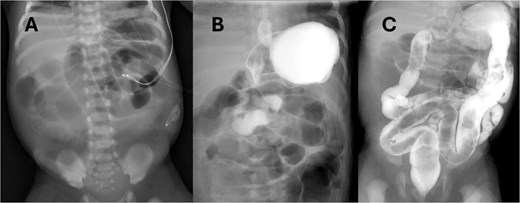

On day of life (DOL) 6, she was noted to have a melanotic stool with increased abdominal distension. Repeat AXR showed presumed dilated transverse colon (Fig. 2). There was concern for infectious pathology, however blood cultures, urine cultures, and cytomegalovirus serology later resulted as unremarkable. DOL 10 AXR (Fig. 2) illustrated new linear lucencies, possible pneumatosis, and patient was taken to the operating room.

Progression of AXR. Note the changing bowel gas patterns. (A) DOL 2. (B) DOL 5. (C) DOL 6. (D) DOL 10 with concern for pneumatosis.

AXR is a useful diagnostic tool in early evaluation of intestinal atresia. Duodenal atresia, which has a different etiology than small bowel atresia, presents with the diagnostic "double bubble" on AXR. When the atresia is located more distally in the jejunum, the AXR will have more than two bubbles. The patient presented failed to have any of the classical findings of obstruction due to incomplete blockage of the intestine. The AXR shown in Fig. 2 clearly demonstrates a large amount of air passing through the intestine without an obvious area of obstruction.